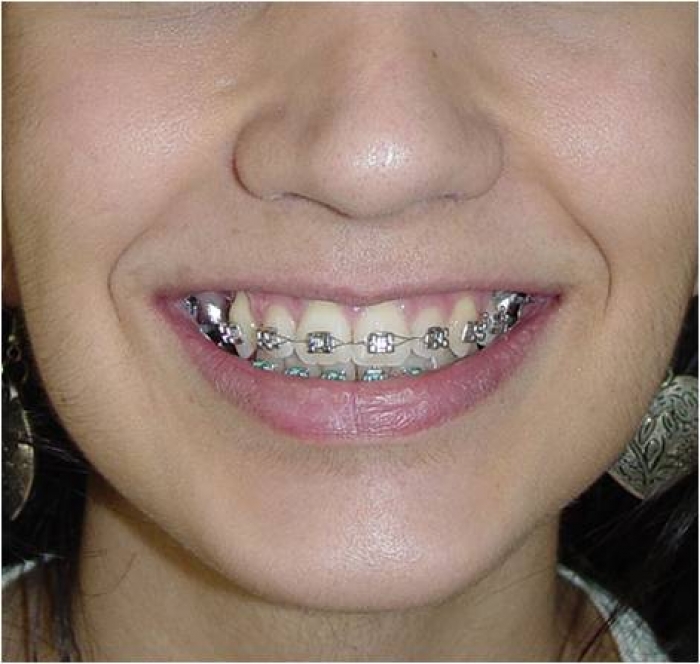

Sorriso inicial